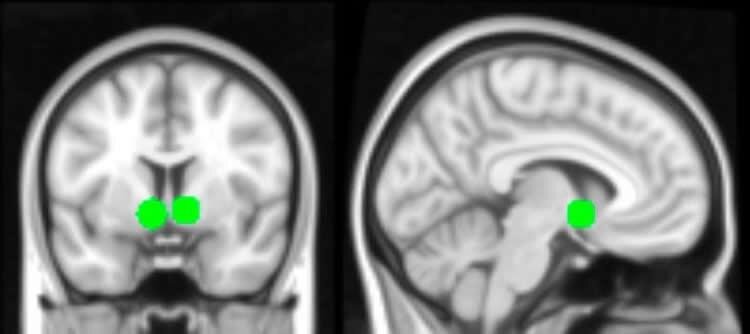

Два снимка мозга. Зеленым выделено прилежащее ядро, центр системы вознаграждения мозга. Эта область была более активна, когда подростки видели фотографии себя и других подростков, лайкнутые  множеством ровесников. Прошлое исследование предполагает, что эта область наиболее активна в юности.

Особенно активна была часть полосатого тела, называемая прилежащим ядром — элемент системы вознаграждения мозга. Считается, что в юности она особенно чувствительна. Когда подростки видели свои фото со множеством лайков, исследователи так же замечали активность в области «социального мозга» и областях, связанных со зрительным вниманием.